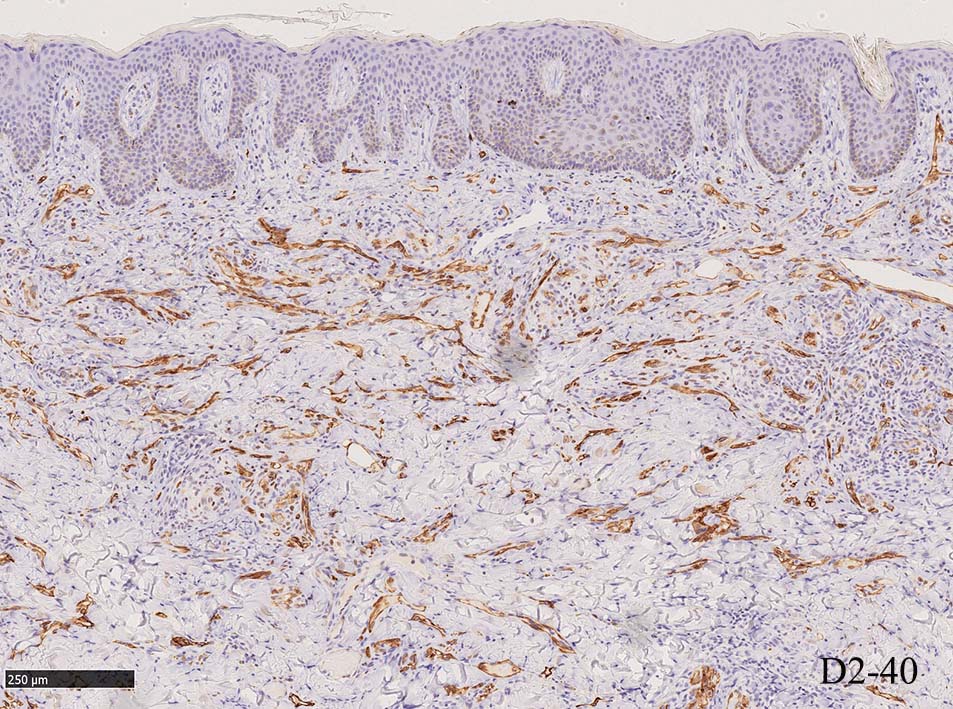

免疫染色, 分子病理学的検査

増生細胞はCd31, CD34, Factor Ⅷ, D2-40などが陽性を示す.

HHV-8の潜伏期関連抗原(HHV-8 Latency-associated nuclear antigen: HHV-8 LANA)が市販されており, 核が点状に染色される陽性所見がKaposi肉腫の確定診断に必須となっている.